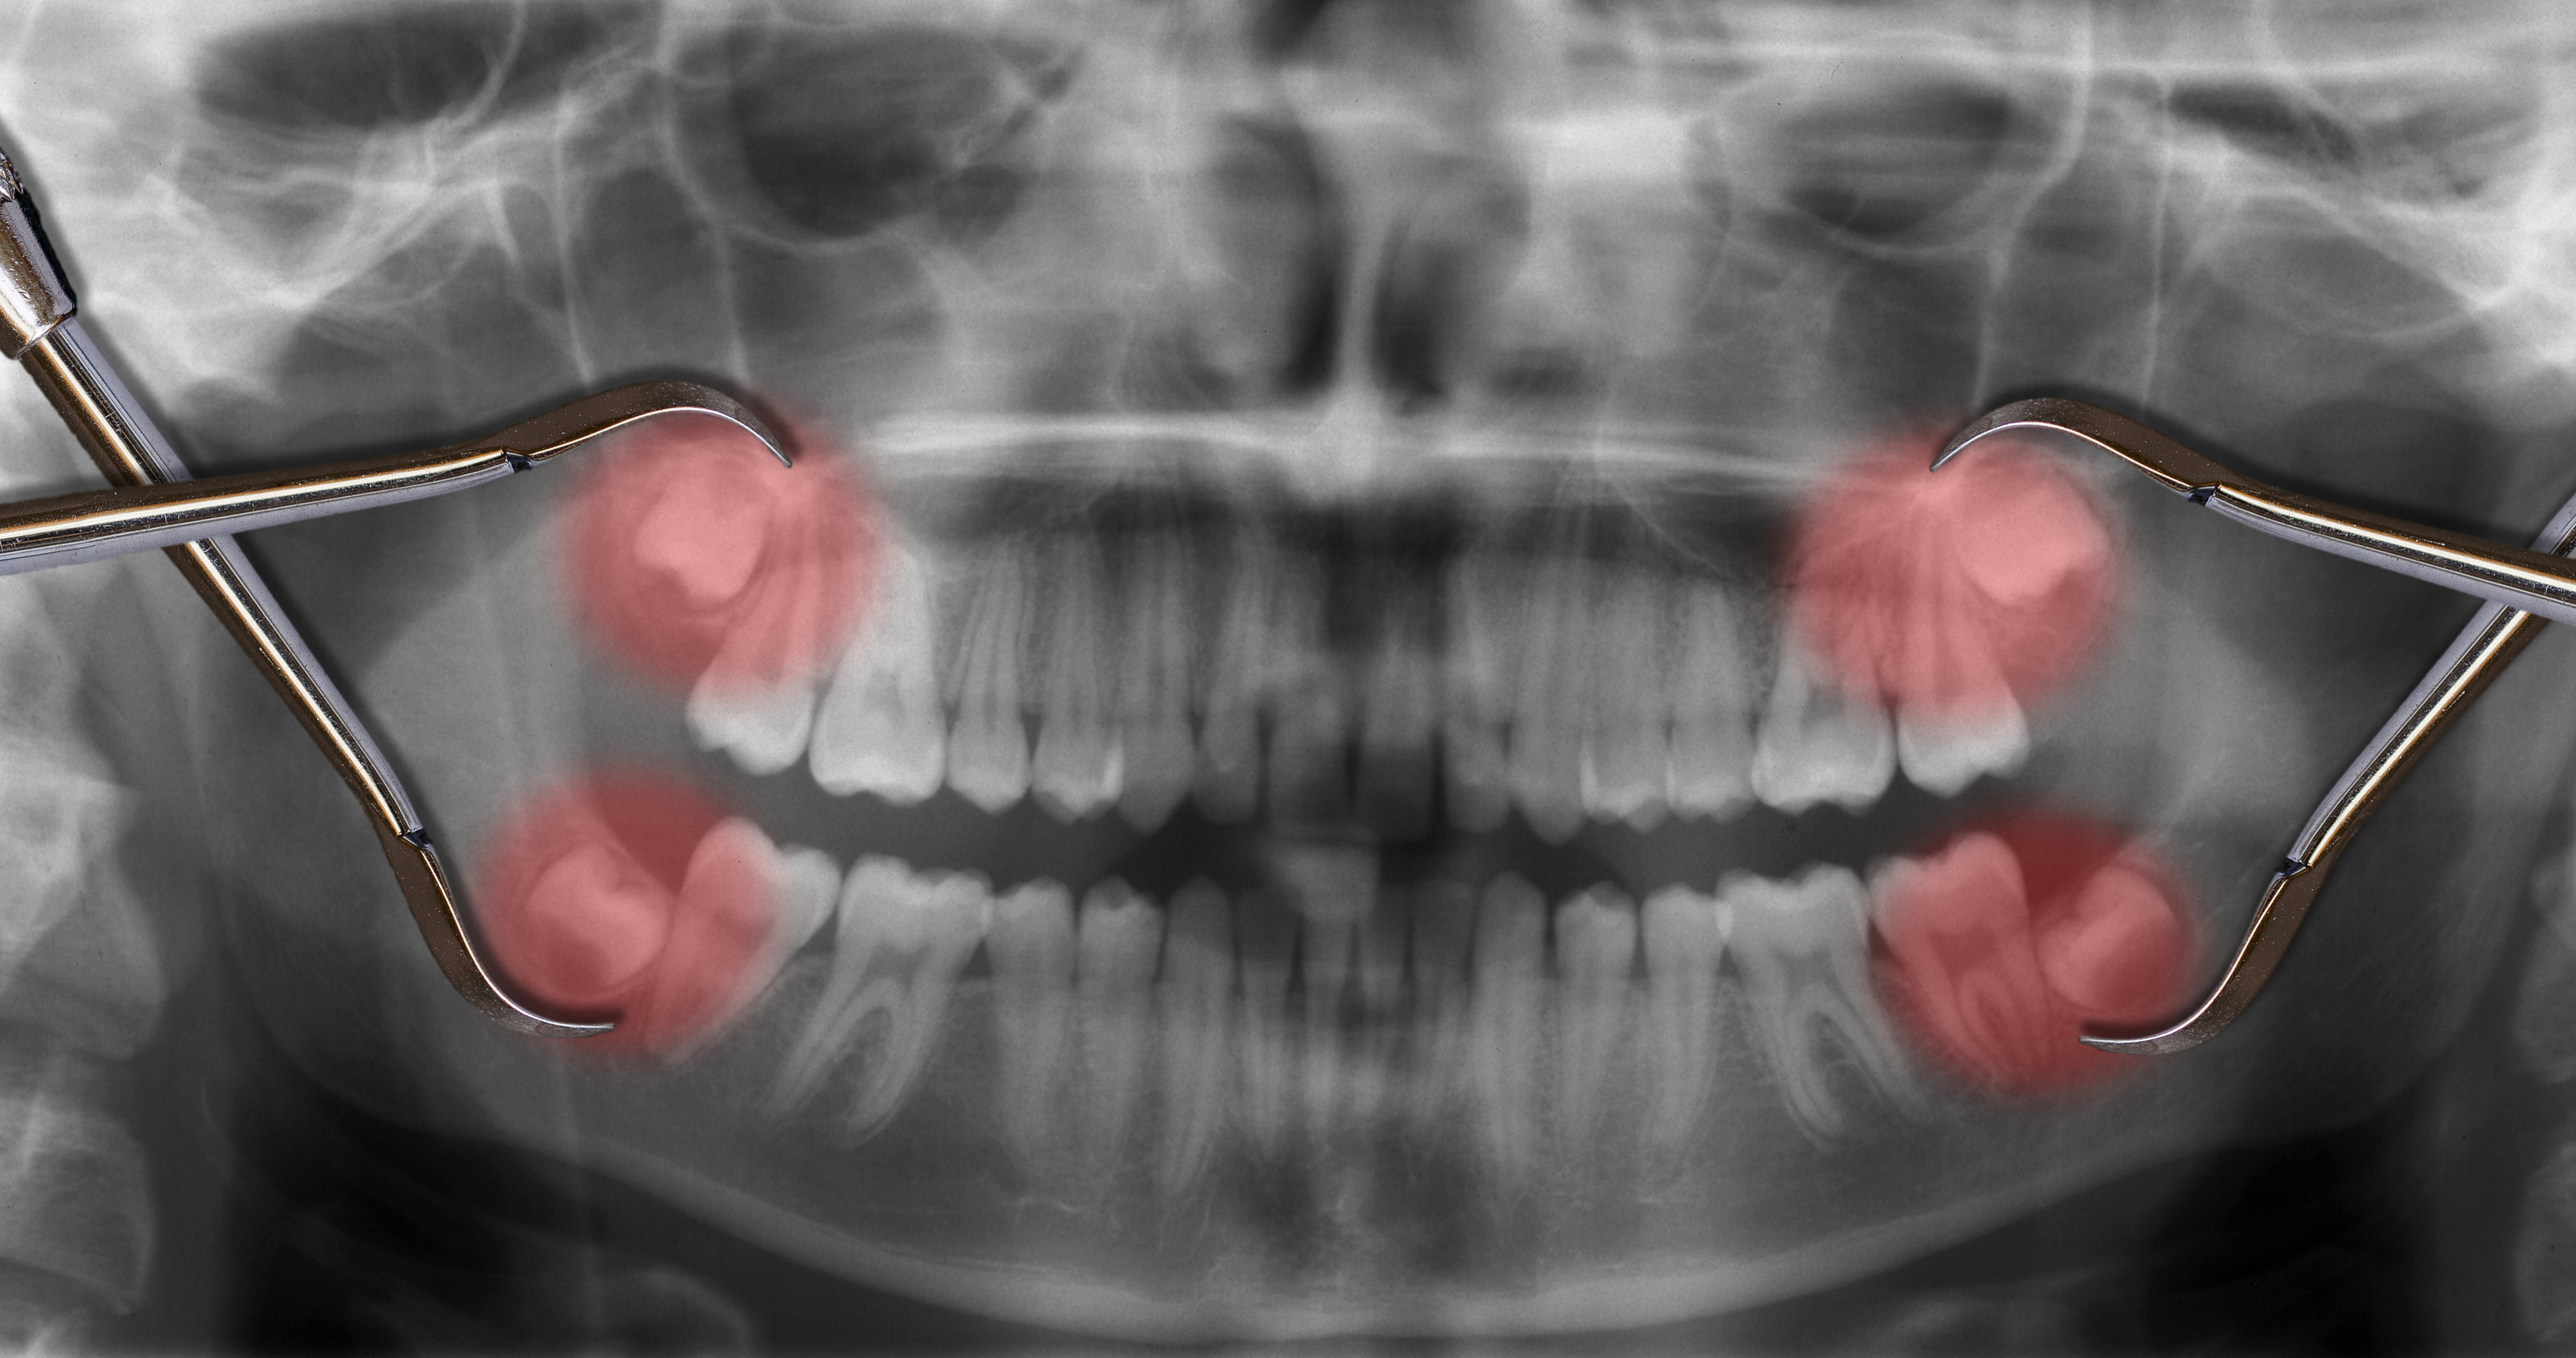

· Диагностика: для получения полной картины необходимо сделать компьютерную томографию (КТ зубов). Это позволяет нам увидеть точное расположение зубов, корней, состояние костной ткани, близость нервов и пазух.

2. Нужно ли делать КТ зубов перед удалением? Да. Компьютерная томография (КТ) позволяет врачу увидеть точную форму и расположение корней, состояние кости вокруг зуба, близость гайморовых пазух и нервов.

6. Обязательно ли удалять зубы мудрости? Нет. Удалять «восьмёрки» нужно, если они:

· Растут вбок, упираются в соседний зуб (могут вызвать кариес).

· Не до конца прорезались (ретинированы), вызывая воспаление десны.

· Провоцируют скученность зубов, напирая на зубной ряд.

· 3D-снимок зубов, на котором максимально информативно видно состояние костной ткани, зубов находящихся в ней, расположение нервов и прочее. Современная стоматология невозможна без использования подробного 3D-снимка.